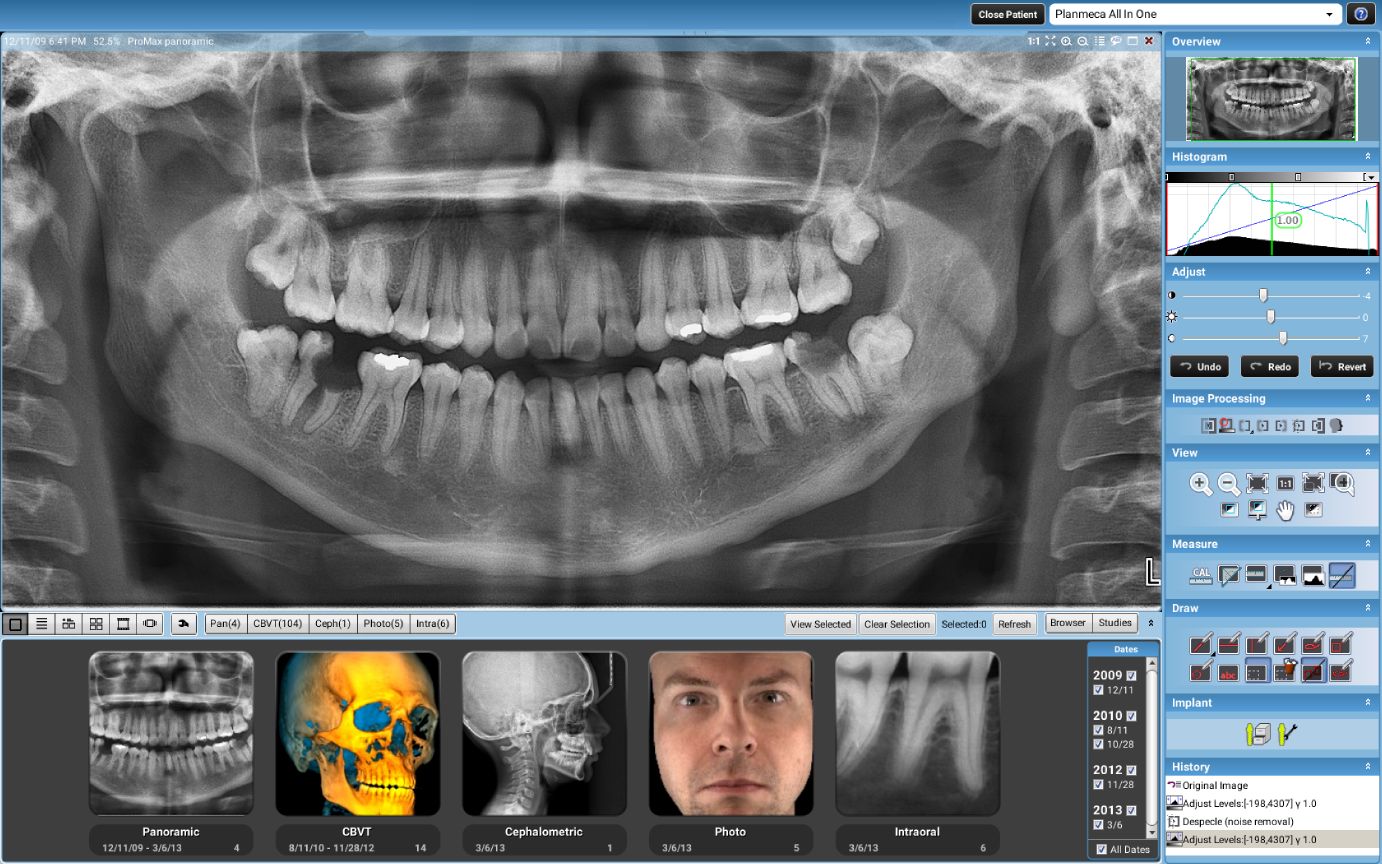

3D snimanje zuba, poznato kao konusni snimak (Cone Beam Computed Tomography – CBCT), pruža detaljan trodimenzionalni prikaz zuba, vilice i okolnih struktura. Ovaj napredni rendgenski postupak omogućava visoku preciznost u dijagnostici i planiranju tretmana, kao što su implantati, ortodontski aparati, lečenje korena i hirurške intervencije. Korišćenjem Planmeca aparata, CBCT omogućava detaljnu analizu čak i najmanjih struktura, što pomaže stomatolozima da donesu tačne i efikasne odluke za svaki specifičan slučaj.

Količina zračenja tokom 3D snimanja zavisi od veličine skenirane oblasti i veličine vokselâ (voxel size). Za aparat Planmeca ProMax 3D Mid, koji je poznat po visokoj preciznosti uz smanjeno zračenje, prosečna doza zračenja za 3D snimanje zuba je približno 10–20 mikrosiverta (µSv). Ovo je značajno niže u poređenju sa tradicionalnim CT snimanjima, koja mogu imati doze zračenja od 100–200 µSv.

3D snimci kao na sajtu.

3D - SNIMCI